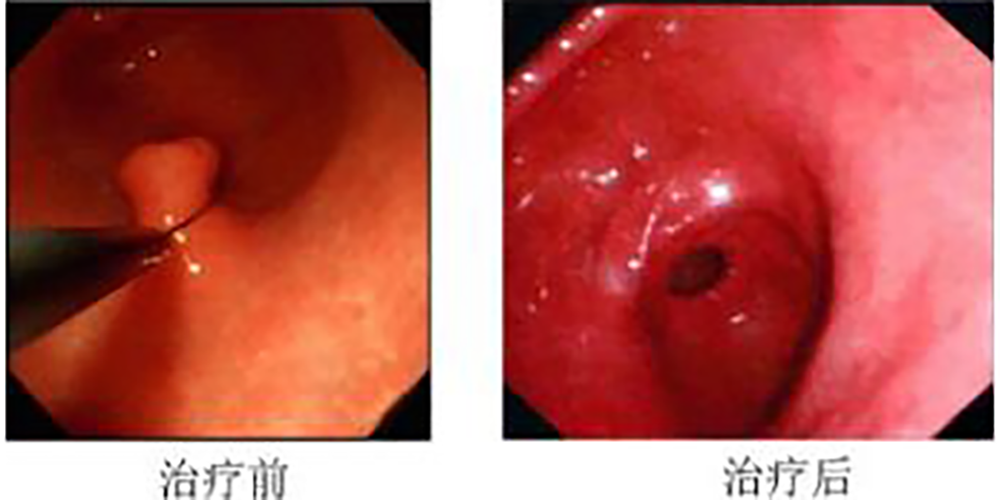

胃息肉治療前後